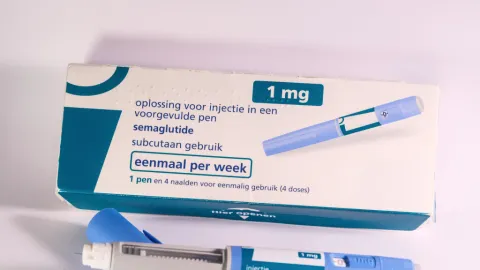

¡Alerta! Cofepris Advierte sobre Lote Falsificado de Ozempic en México: Riesgos para Tu Salud y Cómo Identificarlo